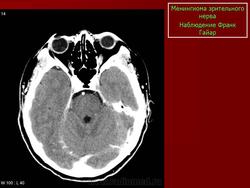

КТ-семиотика

На КТ срезах без контрастного усиления менингиома зрительного нерва выглядит изоденсной. Типично наличие линейных или точечных обызвествлений. Симптом «трамвайных рельс» отражает накопление КВ по сторонам гиподенсного зрительного нерва или наличие обызвествлений в структуре опухоли. Как правило, наиболее дистальная часть зрительного нерва, в месте его вхождения в глазное яблоко, не содержит обызвествлений.

При исследовании необходимо определить расположение бляшковидной менингиомы относительно бугорка турецкого седла и пластинки клиновидной кости, так как данный тип опухоли может распространяться интракраниально через канал зрительного нерва. КТ не позволяет адекватно визуализировать интракраниальное распространение опухоли, которое может привести к развитию двусторонней слепоты.